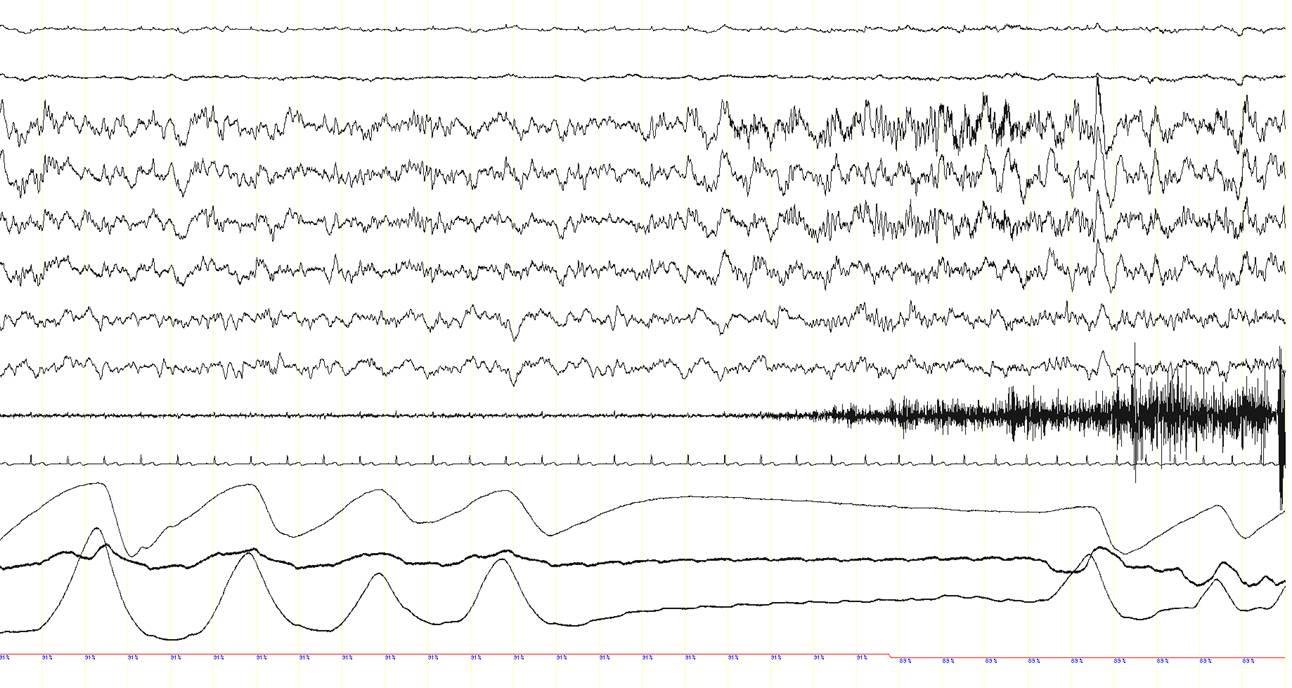

A 63 year-old man was diagnosed with obstructive sleep apnea syndrome because of habitual heavy snoring with breathing pauses during sleep, occasional awakenings and mild excessive daytime somnolence. The patient also complained of recurrent episodes of sudden dizziness, pallor, sweating, and sometimes pain in the right shoulder, either awake or during sleep. An electroencephalography (EEG), brain CT scan and cardiac exercise stress test revealed normal findings and the nature of these episodes had remained elusive. A baseline polysomnographic (PSG) study showed frequent obstructive sleep apneas, particularly in the supine position (apnea-hypopnea index in this position: 33/hour; not shown here). A subsequent continuous positive airway pressure (CPAP) titration PSG study was performed. With a CPAP pressure of 7 cm H2O obstructive events were well-controlled. Suddenly, however, the patient presented an apnea (panel A, between arrows) with a change in the EEG signals. This is shown in the three consecutive 30-second epochs (panel A, B and C). In panel D, a 20-second epoch of the event is shown. Can you describe what is happening here?

Note the presence of epileptogenic activity on the EEG channels just after the onset of the central apnea while the patient is in NREM sleep (N2). A rhythmic 8-9 Hz EEG activity is recorded in the left frontal area (red arrow, F3-REF), which rapidly spreads over the rest of the hemisphere and to the contralateral side (green arrow), and progressively increases in amplitude and decreases in frequency to theta (4-5 Hz) and finally delta ranges (2-3 Hz) (blue arrows). This ictal EEG rhythmic activity lasted approximately 1 minute (end of the ictal rhythm: red arrow in the third epoch; panel C). Remarkably, during this seizure with an initial ictal central apnea, oxyhemoglobin saturation dropped to 73%. The patient also presented repetitive chewing movements (see the artefact caused by masticatory movements in the EEG channels; red asterisks), but overt convulsions or other abnormal movements or behaviours were not recorded. The patient was unaware of this seizure and did not recall any event during the night the following morning.